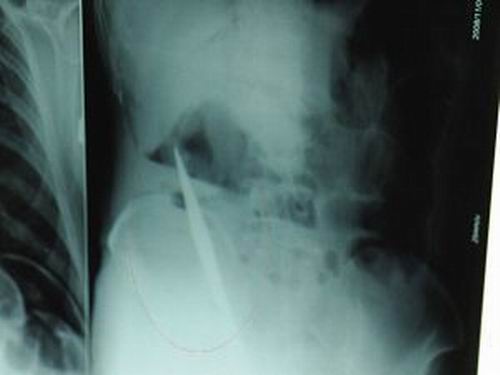

X光片上,尖刀清晰可見(jiàn)。

從男子體內(nèi)取出的尖刀足足有19厘米長(zhǎng)。

江蘇銅山一58歲男子因服毒被送到醫(yī)院搶救,可醫(yī)生采取搶救措施后卻發(fā)現(xiàn)效果不佳。后來(lái)經(jīng)細(xì)致檢查,醫(yī)生有了個(gè)驚人的發(fā)現(xiàn),該男子的體內(nèi)竟然有一把尖刀,醫(yī)生通過(guò)手術(shù)將位于其腹部右側(cè)橫結(jié)腸下緣的尖刀取了出來(lái)。這把尖刀足足有19厘米長(zhǎng)!據(jù)醫(yī)生推測(cè),這把刀應(yīng)該是從肛門推進(jìn)體內(nèi)的,不知男子為何想以如此殘酷的方式結(jié)束自己生命。由于搶救及時(shí),該男子已暫時(shí)脫離危險(xiǎn)。

昨天(11月6日)上午,記者在徐州礦務(wù)集團(tuán)總醫(yī)院重癥監(jiān)護(hù)室見(jiàn)到了這名男子,目前他雖然已經(jīng)恢復(fù)了意識(shí),但還不能開(kāi)口說(shuō)話,需要呼吸機(jī)輔助呼吸。據(jù)醫(yī)生介紹,4日中午12時(shí)左右,這名男子因服毒輕生被緊急送到醫(yī)院進(jìn)行搶救,之前,這名男子已經(jīng)在當(dāng)?shù)剜l(xiāng)鎮(zhèn)醫(yī)院進(jìn)行了近20小時(shí)的治療,但效果不佳!安∪吮晦D(zhuǎn)院到礦總院時(shí)已神志不清,血壓極低,處于休克狀態(tài)!本茸o(hù)人員給男子洗胃、初步處理以后,發(fā)現(xiàn)男子呼吸急促,于是趕緊給他拍片檢查。結(jié)果讓所有的醫(yī)生大吃一驚,竟有一把尖狀異物橫在該男子腹腔內(nèi)!當(dāng)天下午5時(shí)30分,輕生男子被推上了手術(shù)臺(tái)。經(jīng)過(guò)40多分鐘的手術(shù),該男子腹腔被打開(kāi),手術(shù)醫(yī)生發(fā)現(xiàn),男子體內(nèi)的金屬狀異物竟然是一把長(zhǎng)19厘米的尖刀!

醫(yī)生告訴記者,手術(shù)后,醫(yī)生在病人身上并未發(fā)現(xiàn)刀痕,最后,經(jīng)過(guò)檢查發(fā)現(xiàn),在該男子直腸處找到穿孔。醫(yī)生從醫(yī)學(xué)角度分析后認(rèn)為,這把尖刀應(yīng)該是從肛門插入直腸的。